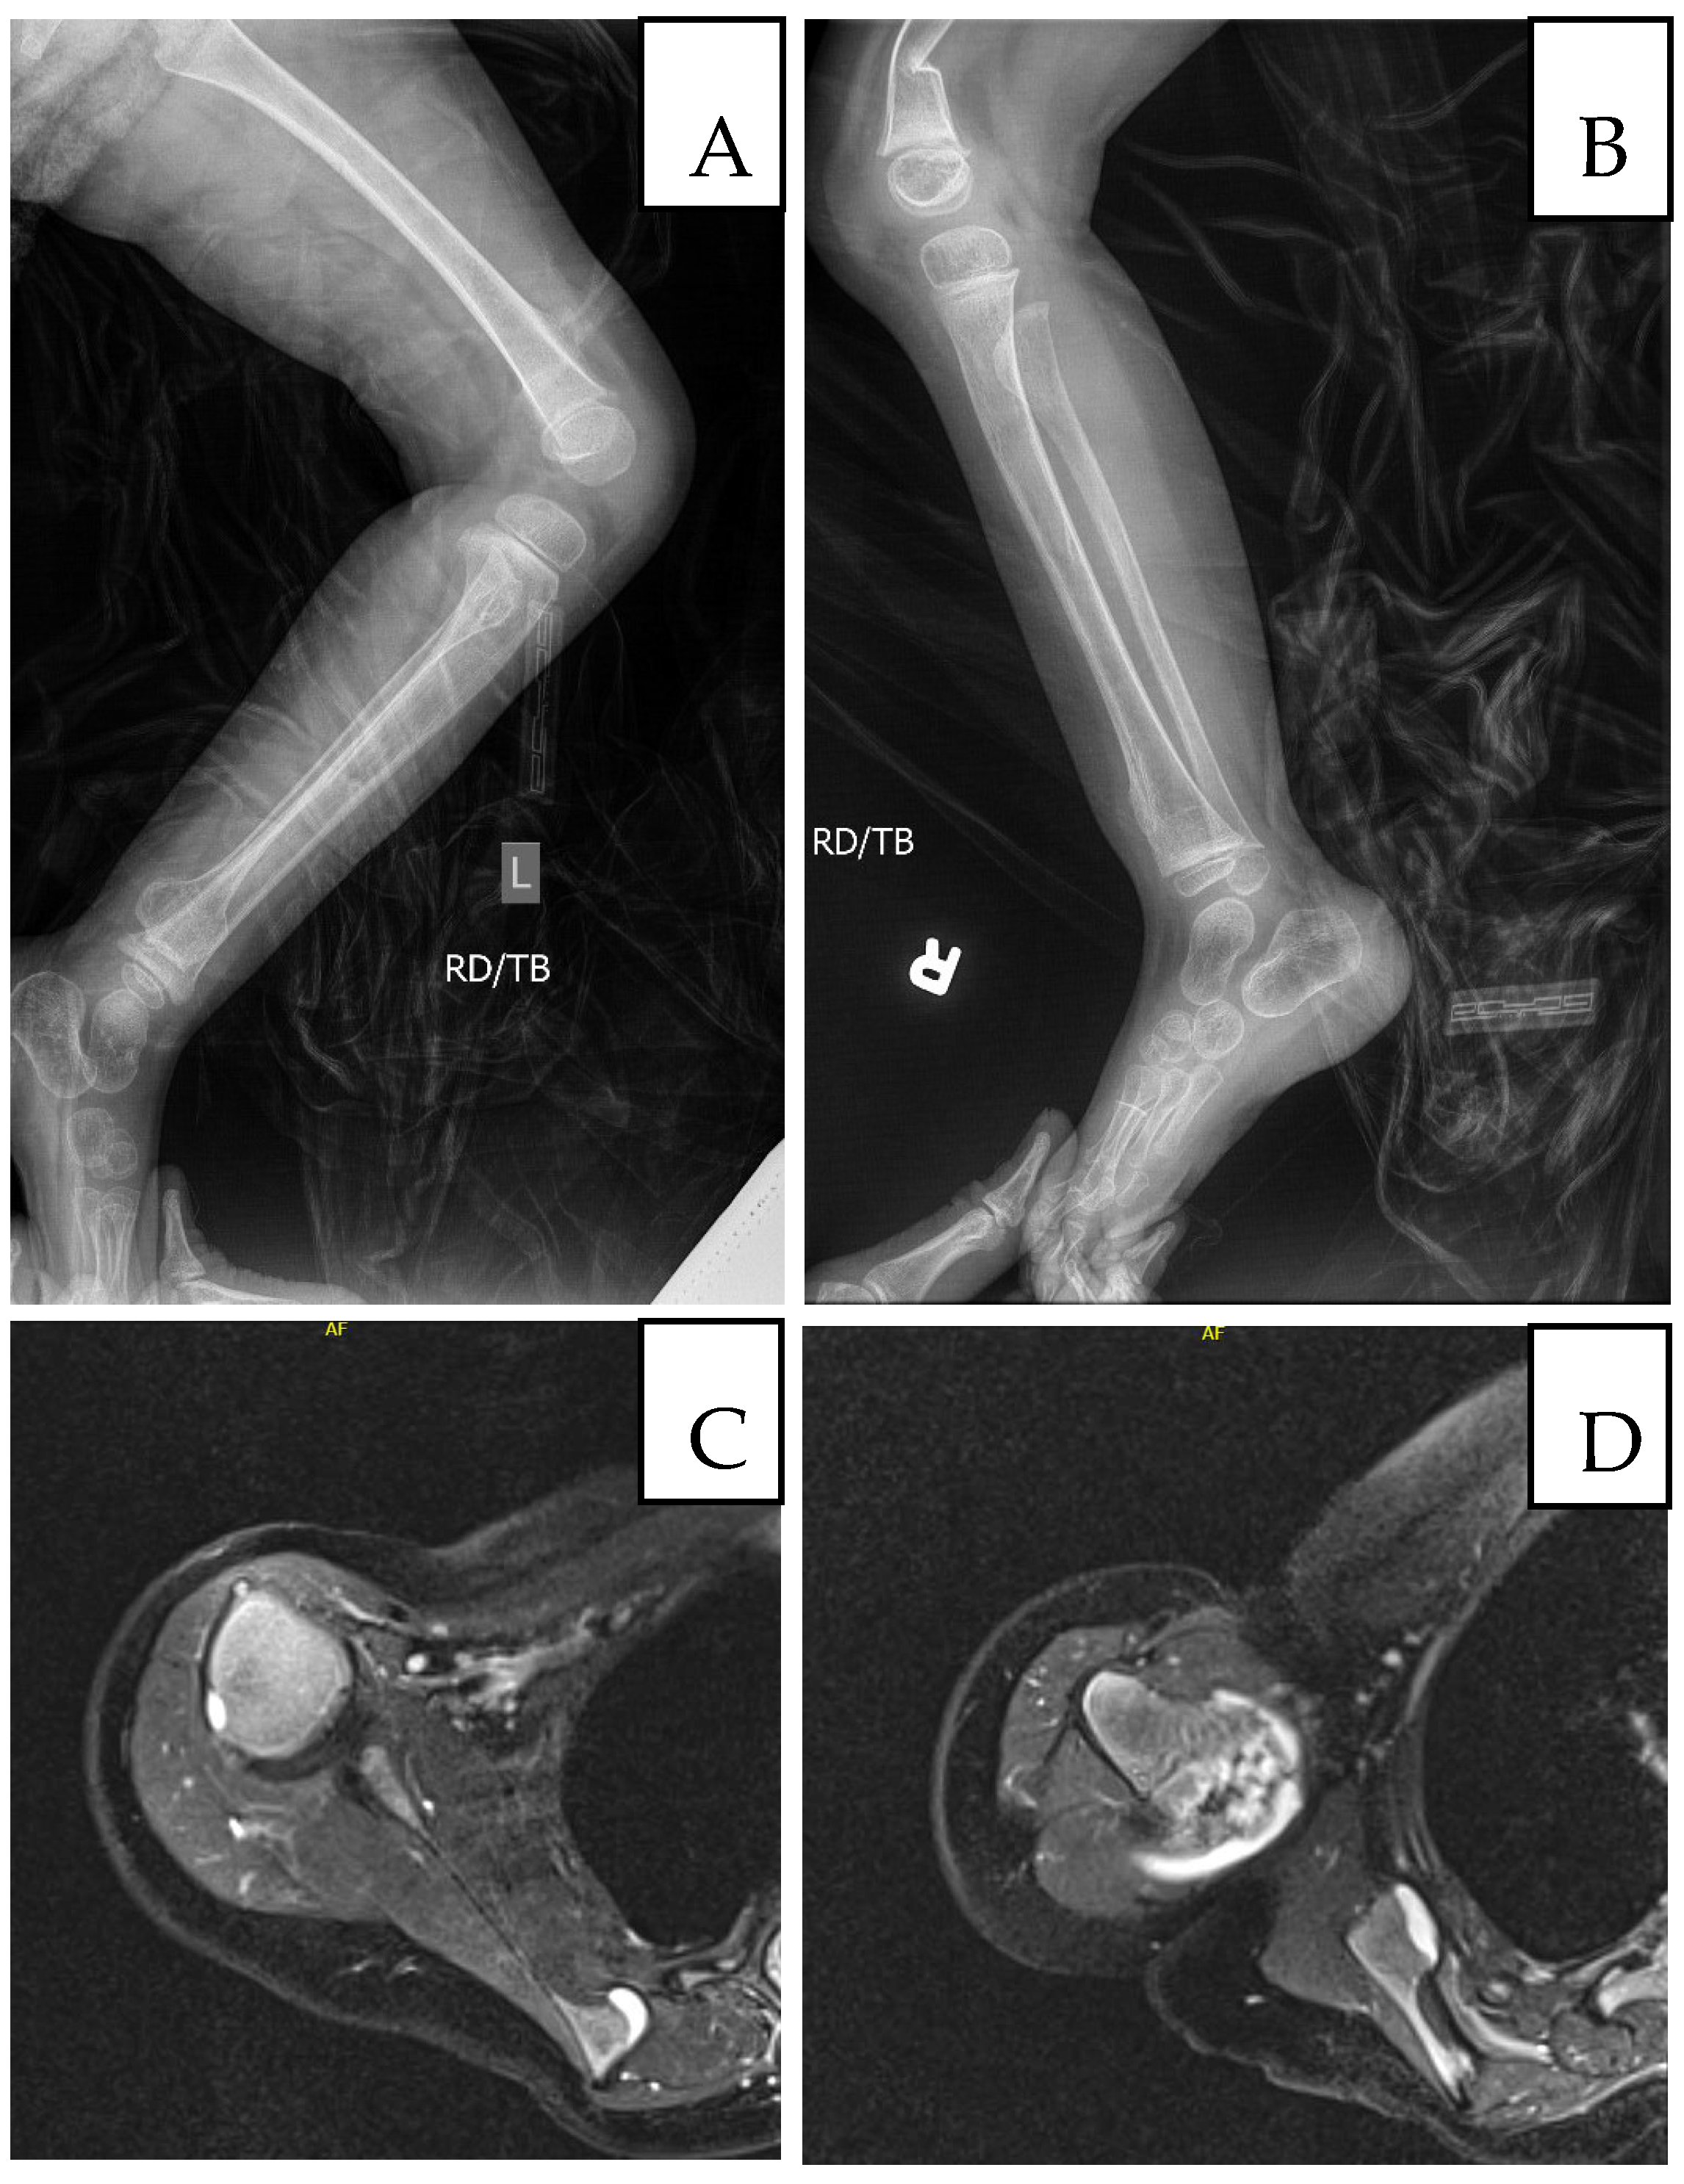

Figure 3.

Imaging at age 5: (A) Left femur/tibia/fibula X-ray with sessile osteochondromas; (B) right tibia/fibula X-ray (comminuted distal right femur fracture shown); (C) MRI, medial border of left scapula; (D) MRI, head of left humerus and lateral left scapula.

At age three, she sustained a left wrist fracture; at age four prior to returning to the genetics clinic (24 October 2023), she sustained a left distal radial and distal right clavicular fracture. During the visit, the mother reported that she exhibited distractibility and reduced speech clarity but no other significant global developmental concerns. Overlapping toes, intoeing, and bone pain had worsened. She had a history of low muscle tone and strength for which she was receiving physical and occupational therapy. She subsequently underwent excision of a left femoral osteochondroma. Growth parameters tracked between the 10th and 50th percentiles for girls in the general population, but between the 80th and 95th percentiles relative to Cornelia de Lange syndrome norms. On physical exam, besides microcephaly, protruding ears, bulbous nose, thin upper lip as described in the previous visit, additional findings including sparse, wiry, and coarse scalp hair, synophrys with lateral thinning of eyebrows, prominent nasal bridge, short upturned nose, anteverted nares and low-hanging columella, thin upper lip, long philtrum, downturned corners of the mouth, overlapping toes, thoracic kyphosis and winged scapulae with posterior protrusion of the superomedial left scapula and acromioclavicular region, flat feet with overlapping toes and osteochondromas located on the internal side of the foot (Figure 1). MRI revealed non-expansile osteochondromas at the right humeral head and scapula; radiographs confirmed bilateral hip dysplasia and additional osteochondromas (Figure 3). A new distal right clavicle fracture was documented. A lower-limb length discrepancy was present (right femur 28 cm; left 25.5 cm).